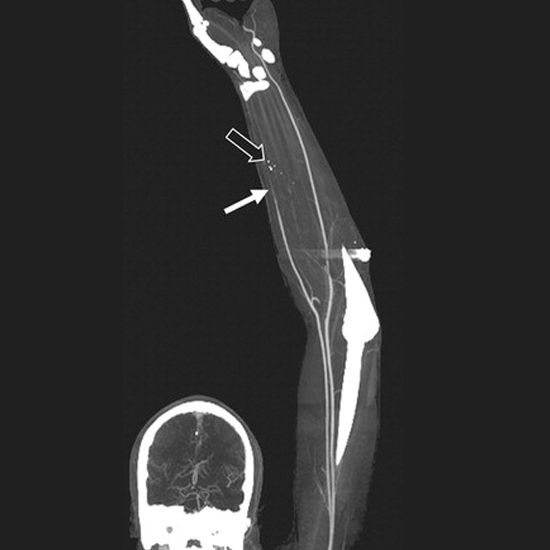

A CT Angiography Arterial Upper Limb is an imaging test that uses a contrast medium to diagnose upper limb arterial injury.

CT angiography (CTA) has evolved into a less invasive alternative to DSA. CTA, in conjunction with standard postprocessing techniques, has enabled rapid, accurate non-invasive evaluation of the upper extremity arterial vasculature.